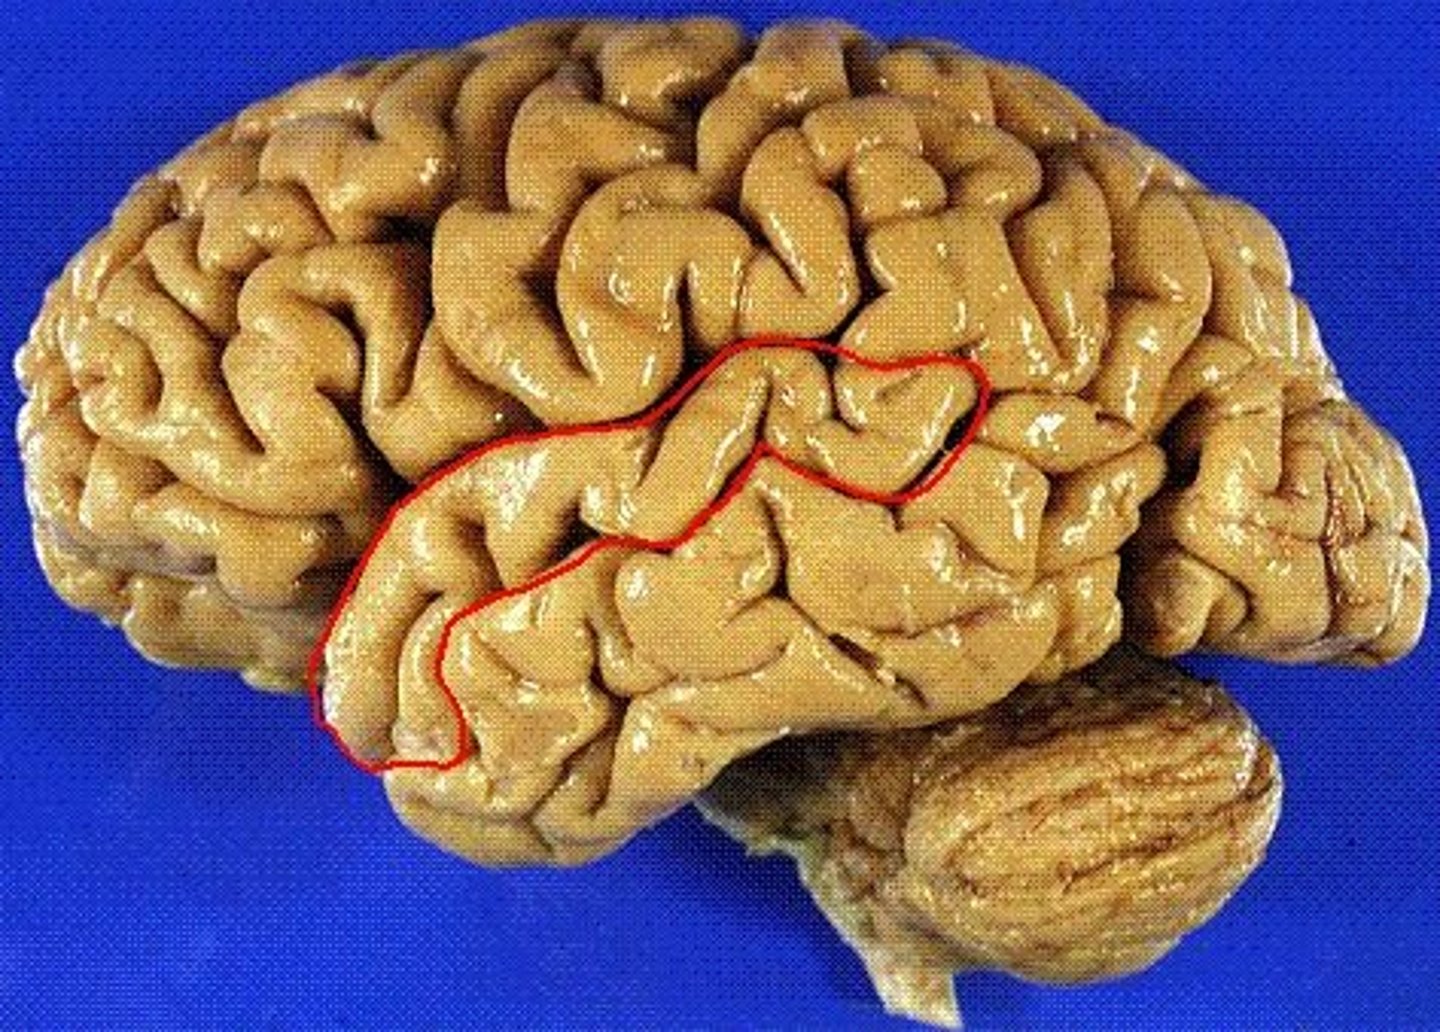

postcentral gyrus

the strip of parietal cortex, just behind the central sulcus, that receives somatosensory information from the entire body

central sulcus

separates frontal and parietal lobes

lateral sulcus

Separates temporal lobe from parietal and frontal lobes